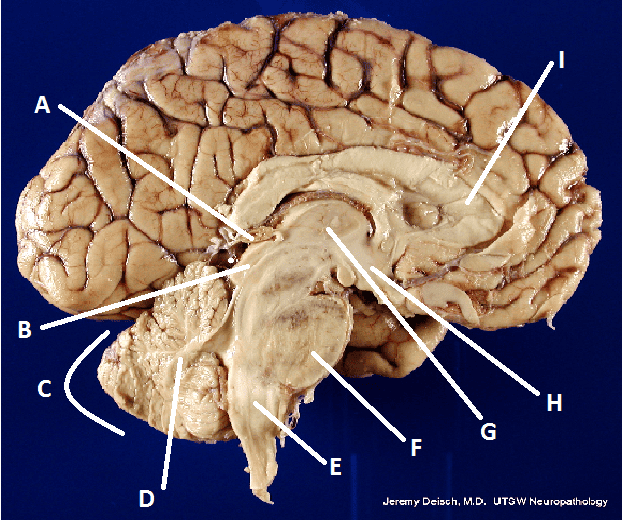

What is A?

Frontal Lobe

What is B?

Parietal Lobe

What is C?

Temporal Lobe

What is D?

Occipital Lobe

What is E?

Parieto-Occipital Sulcus

What is F?

Lateral Sulcus

What is G?

Transverse Sulcus

What is H?

Central Sulcuc